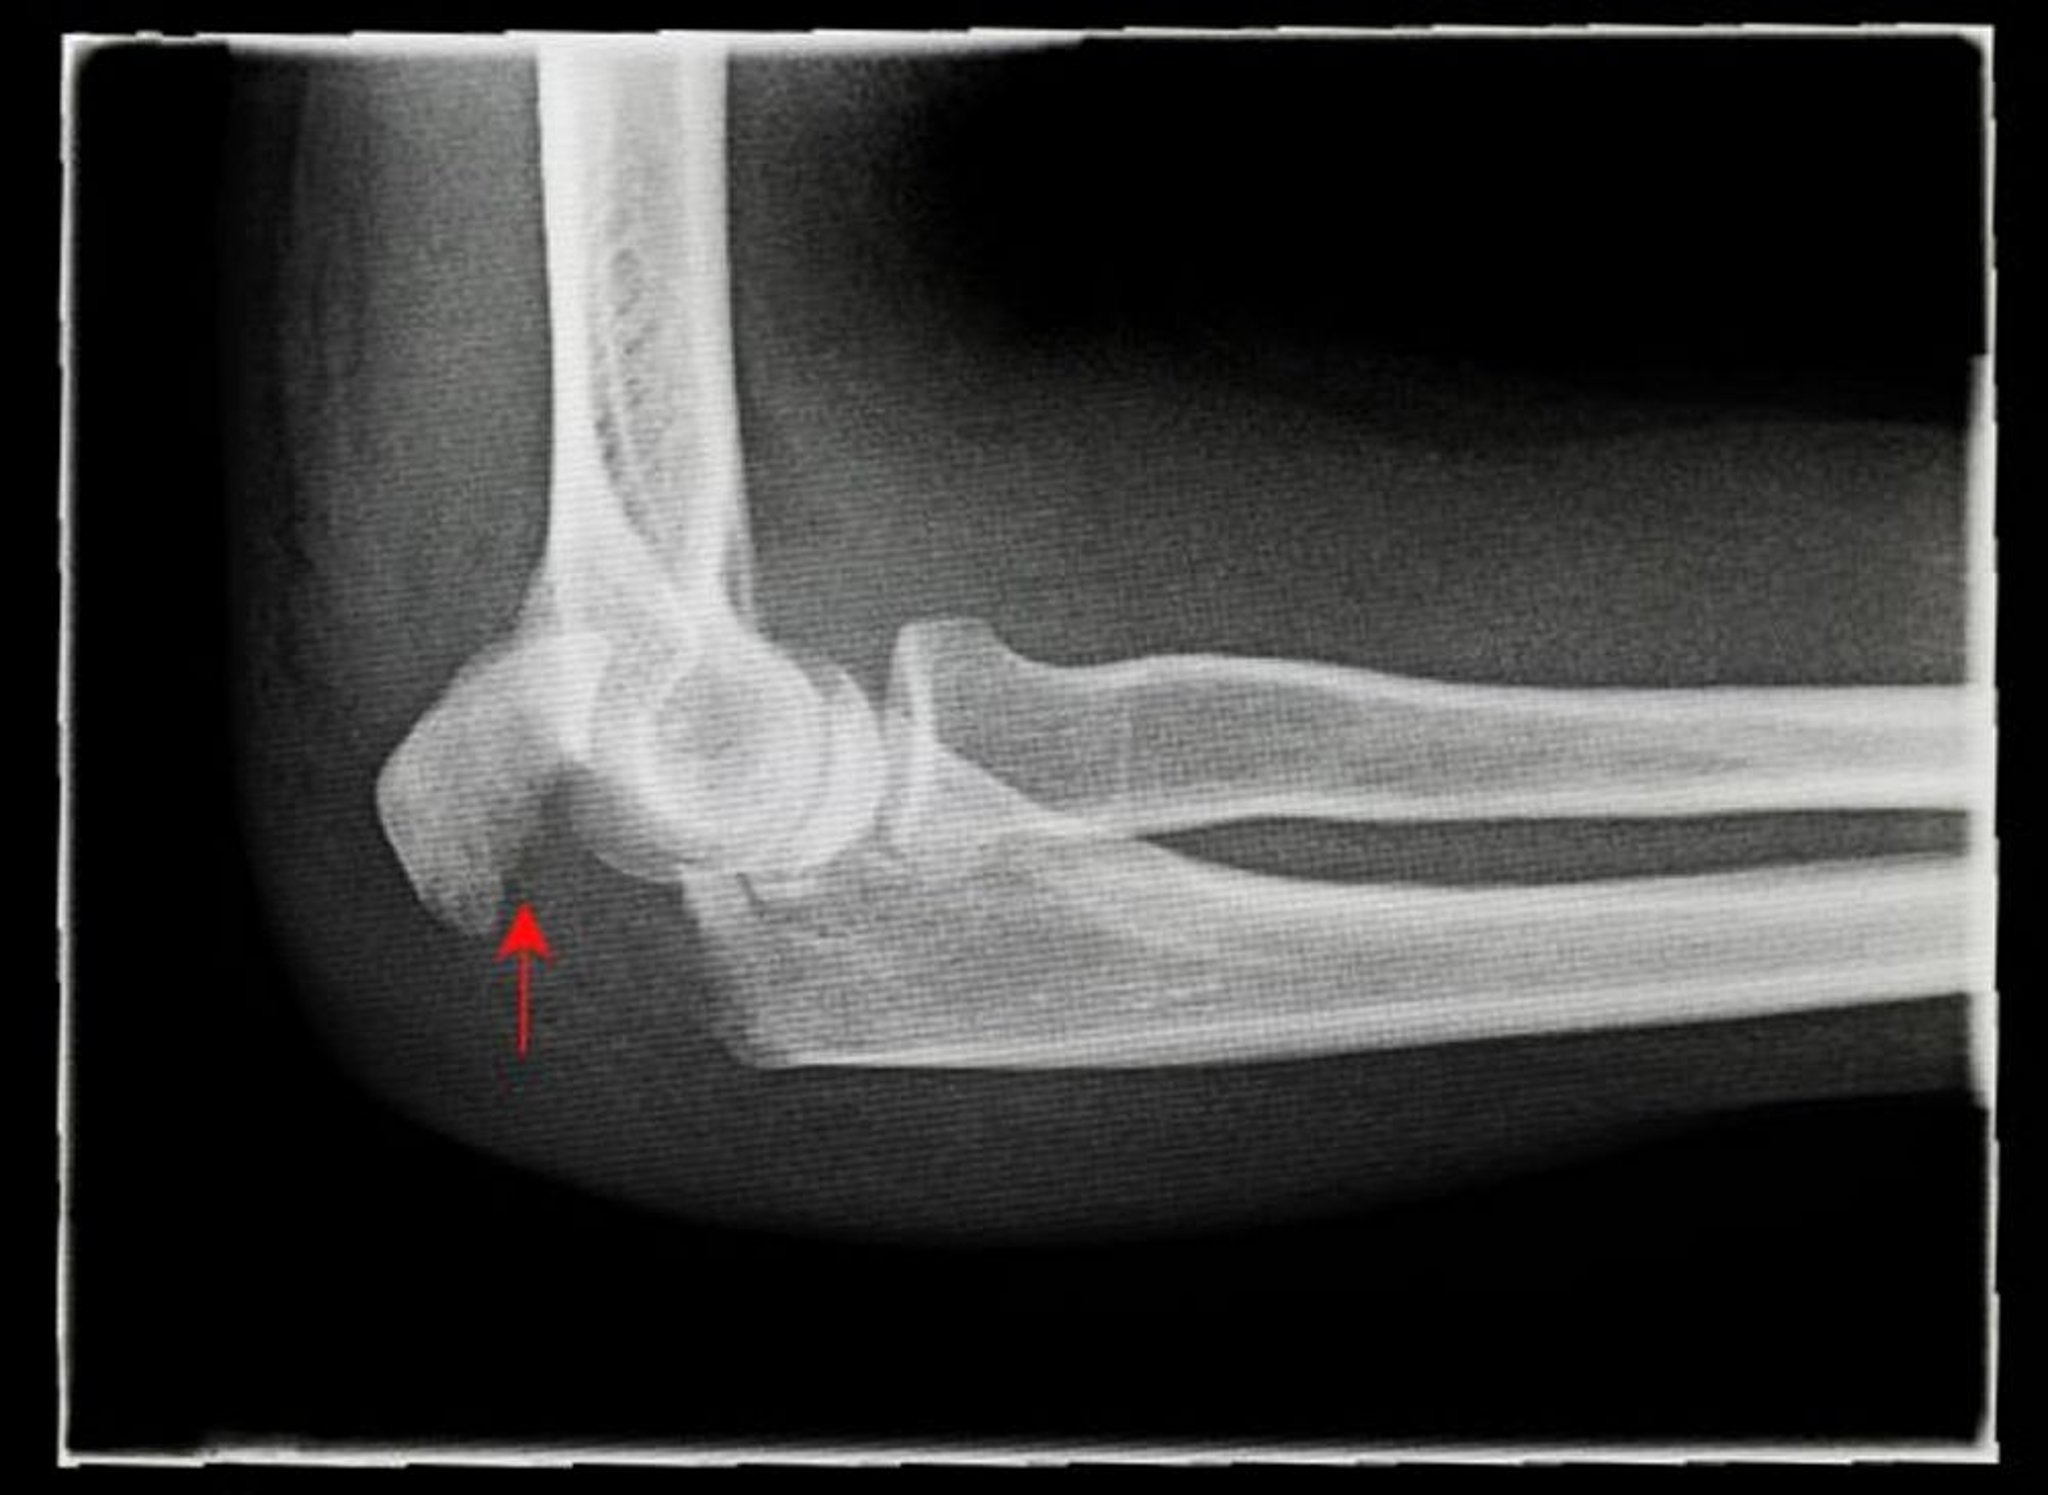

Перелом локтевого отростка со смещением

На этой рентгенограмме показана боковая (латеральная) проекция перелома локтевого отростка со смещением (стрелка).